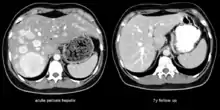

| The CT scan of a patient with peliosis hepatis (left): The follow-up CT (right) after 7 years shows full remission. | |